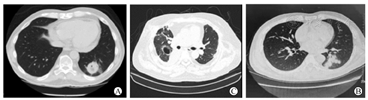

"反晕征"(图3)是肺毛霉病的一种特征性影像学表现[23]。肺毛霉病患者的特征性与非特征性表现同样与患者基础疾病和疾病进展相关;部分肺毛霉病患者也呈非特征性的改变,如:节段性实变、单个或多个结节和肿块、磨玻璃样病变等[28]。临床中,毛霉病特征性的"反晕征"改变在异基因造血干细胞移植受者中更常见[23],而SOT受者则常表现为空洞、实变等非特异性改变[29]。肺念珠菌病、肺隐球菌病的影像学表现缺乏特异性;肺念珠菌病患者影像学常表现为局灶性或多叶性实变,血源性播散患者肺部CT表现为大小不等、多发、边界清楚的结节,部分结节周围伴有"晕征"[30]。隐球菌肺炎的CT表现包括边界清楚的结节实变影。